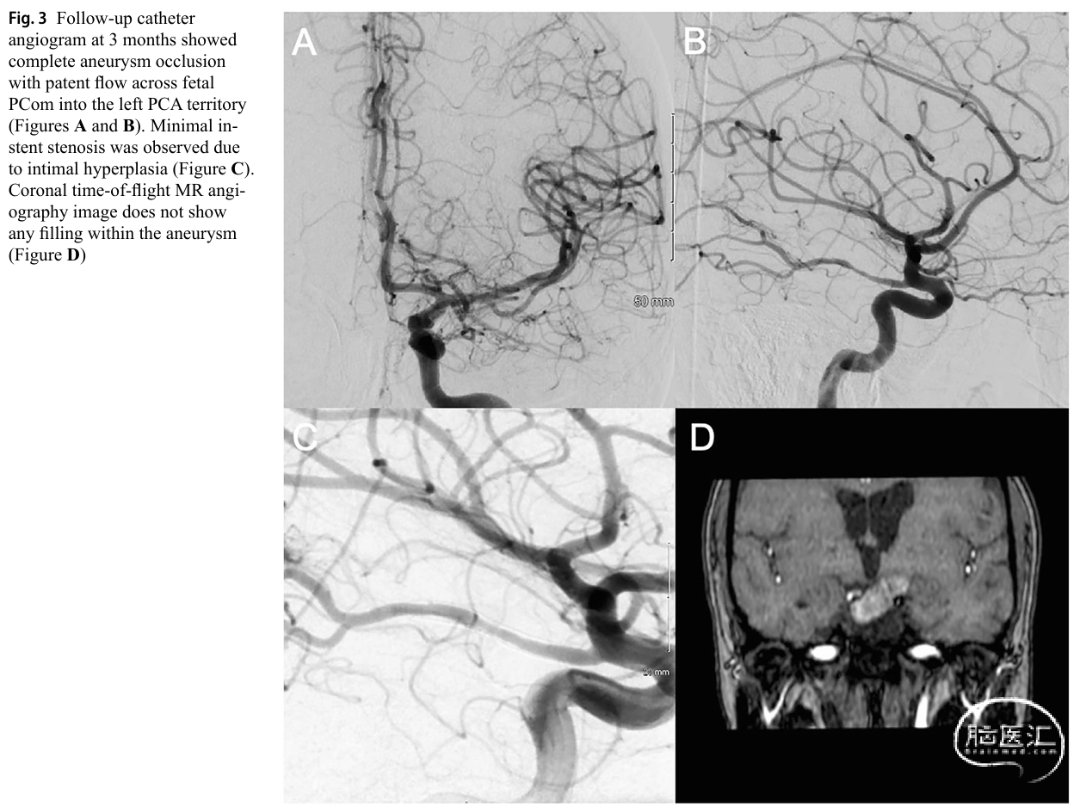

1例60余岁女性患者(合并2型糖尿病、高血脂、吸烟史),左侧近段大脑后动脉大型部分血栓性动脉瘤,采用球囊锚定技术成功部署血流导向支架,术后3个月动脉瘤完全闭塞,无并发症。该案例提示球囊锚定技术在复杂解剖(如胎儿型后交通动脉)中的可行性。